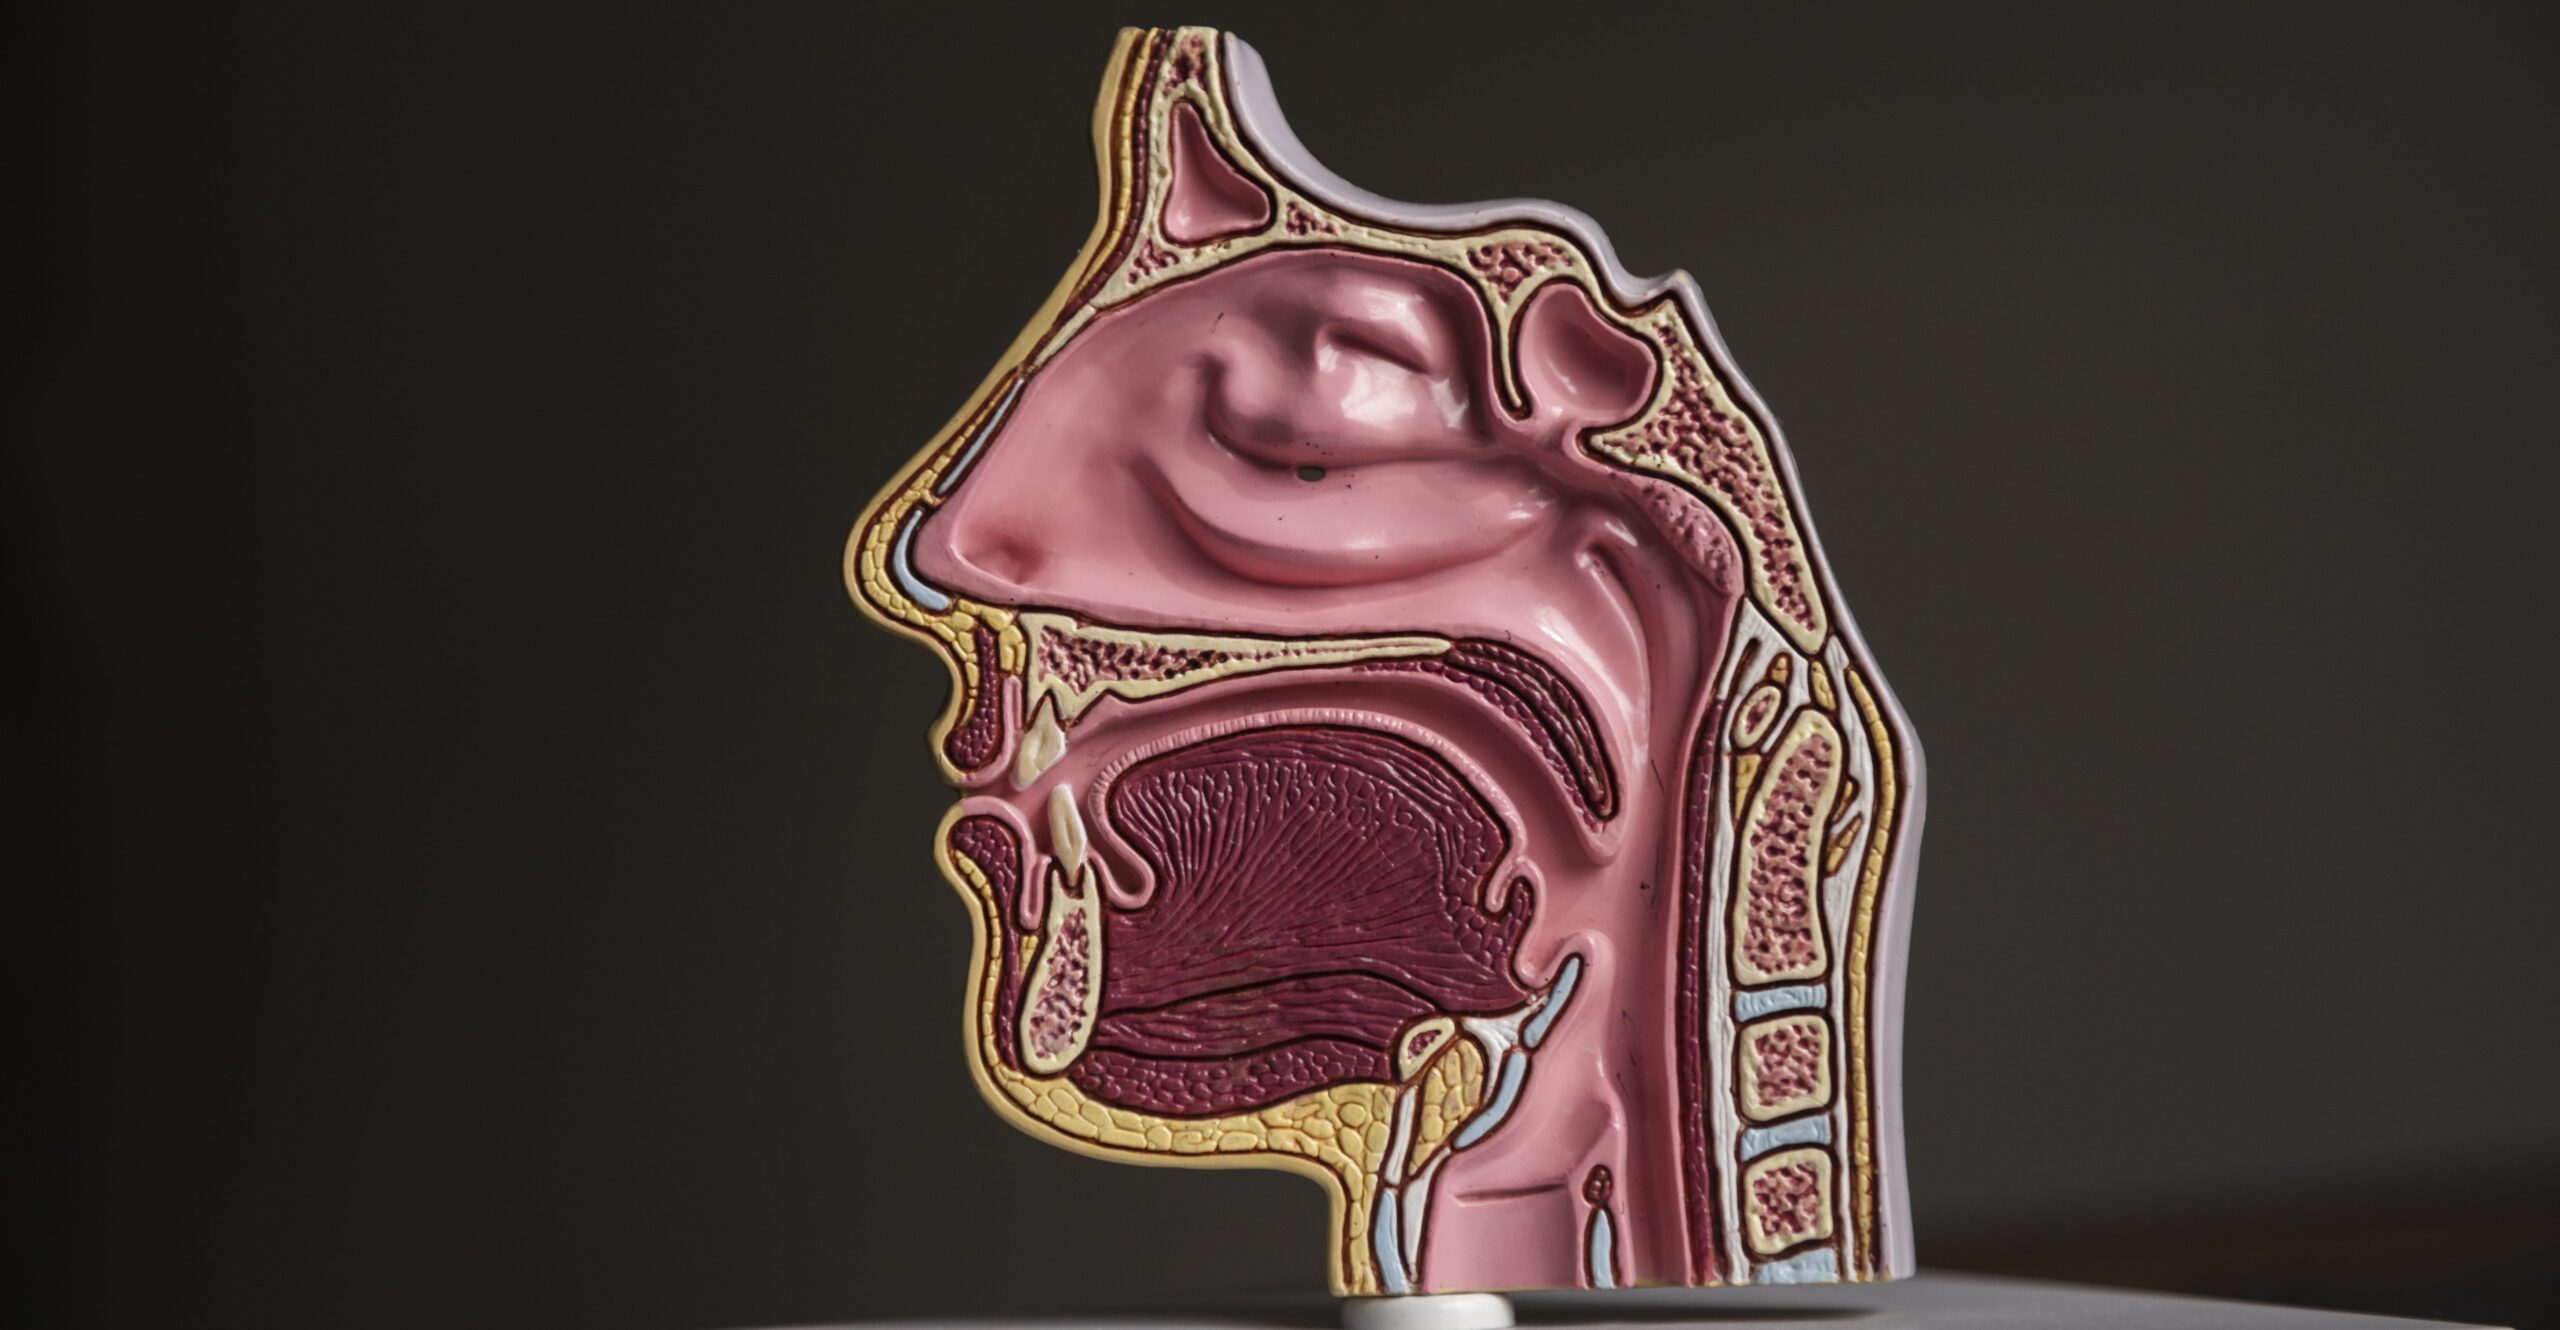

غدد درون ریز و نقش آن ها در بدن

غدد درونریز وظیفه ترشح هورمونها را دارند و این هورمونها فرآیندهای مهم بدن مانند متابولیسم، رشد، تنظیم قند خون و فشار خون را کنترل میکنند.

برخی از مهمترین غدد درونریز عبارتند از:

تیروئید (تنظیم متابولیسم و انرژی)

غدد فوق کلیوی (تنظیم استرس و هورمونهای بدن)

لوزالمعده (کنترل قند خون)

تخمدانها و بیضهها (هورمونهای جنسی)